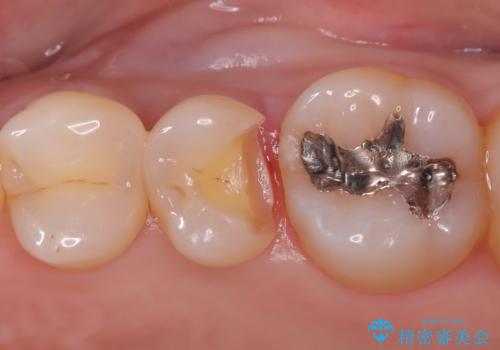

- クリーニング希望で来院されました。お口の中を確認したところ虫歯があり、部分的な詰めものでの修復となりました。材料の性質を説明し、セラミックインレーを選択されました。

接着時にはラバーダム防湿を行っています。